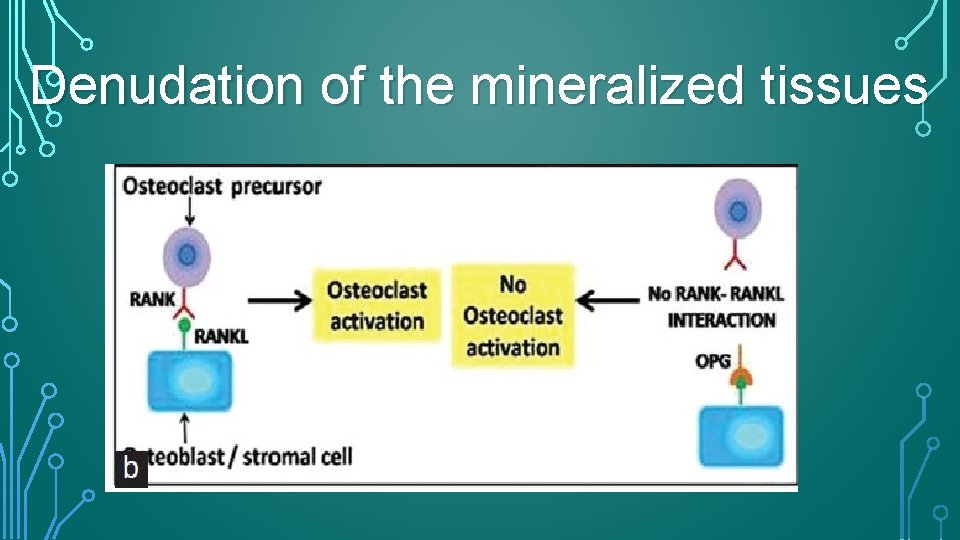

MOLECULAR SIGNALING • the OPG/RANKL/ RANK transcription factor system that controls clastic functions during bone remodeling has also been identified in root resorption. • OPG- osteoprotegrin- prevents binding of RANKL to RANK- prevents activation of osteoclasts • RANKL: receptor activator of NF-κb ligand : responsible for activation of osteoclasts after binding to RANK on the surface of their precursors • RANK: present on the surface of osteoclastic precursors.